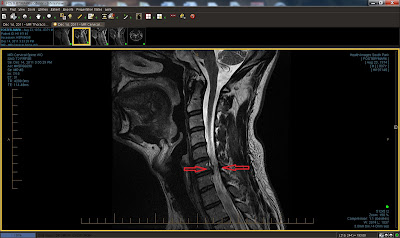

Thoracic Herniated Disc

Thoracic Herniated Disc Pictures